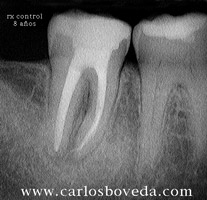

Video de un Retratamiento de Conductos en Una Sesión - (formato Quicktime)